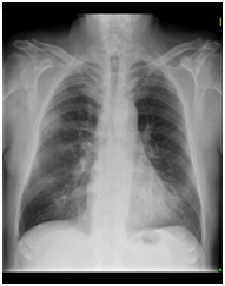

Como primer estudio, normalmente, se realiza un estudio mediante RX para poder observar los campos pulmonares y descartar lesiones evidentes. Sin embargo, en este caso, al haberse realizado ya una RX, se solicita un TC sin contraste para poder observar con detalle el parénquima pulmonar y detectar lesiones en éste.

HALLAZGOS

-Nódulo pulmonar de 2,9 x 2,8 cm,hipodenso, polilobulado, bien definido y de base pleural, probablemente infiltrativo de grasa subpleural.

-Ateromatosis aórtica calcificada. Arterias coronarias: DEA y circunfleja con calcificaciones.

-En cuanto al mediastino, se ven adenopatías de morfología ovoide en región paratraqueal, probablemente malignas. Numerosas adenopatías, algunas de menor tamaño.

-Se detectan ganglios en abdomen, cerca de aorta, aunque no cumplen criterios radiológicos de malignidad.